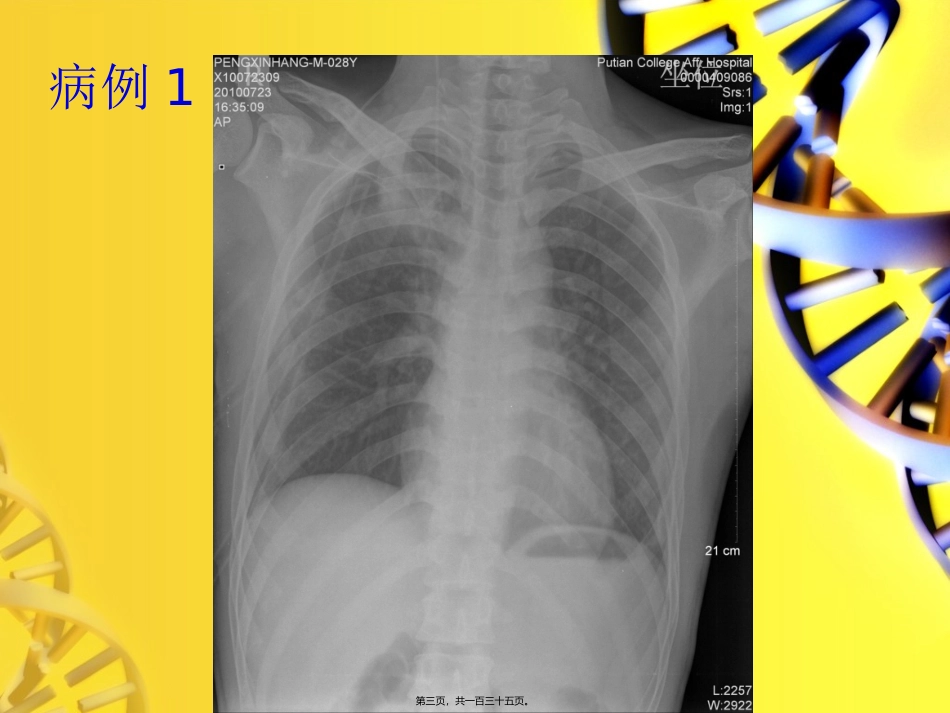

病例讨论第一页,共一百三十五页。病例1病史:•患者,男性,28岁,胸痛1月,偶有咳嗽第二页,共一百三十五页。病例1第三页,共一百三十五页。病例1第四页,共一百三十五页。病例1第五页,共一百三十五页。A.结核球B.肺癌C.炎性肉芽肿D.肺曲霉菌病E.肺转移瘤印象:第六页,共一百三十五页。•结核球病理结果第七页,共一百三十五页。讨论•结核球:干酪性病变被纤维组织包裹而形成的球状病灶•结核球邻近肺野有较多的病灶,即所谓的“卫星病灶〞•引流支气管的管壁平行地增厚引向肺门,但肺门淋巴结一般不肿大第八页,共一百三十五页。主要鉴别诊断--周围型肺癌•结核球与周围型肺癌从病变来源鉴别非常重要,但从X线征象上有时鉴别甚为困难,病变部位大小对鉴别二者有一定帮助,价值不大,在随诊中观察生长情况也只能提供参考价值,关于密度特异性钙化少见也无绝对意义,肿瘤边缘明显的分叶和细短毛刺是肺癌的特殊征象,虽然结核球边缘也可呈波浪状,但无明显切迹,而肺癌切迹多在3个以上,结核球边缘也有几条因纤维化而形成的致密粗长阴影向周围伸展,与肺癌向周围组织浸润形成密度浅而均匀细短毛刺不同,因此,切迹征和毛刺征能代表球形病灶本质及特征,是肺结核球与肺癌鉴别的可靠依据第九页,共一百三十五页。病例2病史:•患者,女性,43岁,左膝关节肿胀半年余,近感疼痛一月余第十页,共一百三十五页。病例2第十一页,共一百三十五页。第十二页,共一百三十五页。第十三页,共一百三十五页。第十四页,共一百三十五页。第十五页,共一百三十五页。第十六页,共一百三十五页。第十七页,共一百三十五页。A.骨肉瘤B.骨巨细胞瘤C.动脉瘤样骨囊肿D.内生软骨瘤E.骨结核印象:第十八页,共一百三十五页。病理结果•骨巨细胞瘤第十九页,共一百三十五页。讨论骨巨细胞瘤是髓内实质性肿瘤,可呈广泛坏死、出血和囊变,目前认为来源于未分化的结缔组织,多发生于骨骺融合之后,具有复发、转移和恶变的趋向。X线:膨胀性多房性偏心性骨破坏,肿瘤局部骨性包壳即骨性关节面,破坏区无钙化和骨化影,一般无骨膜反响CT:骨性包壳,大多数不完整连续,但无包壳外的软组织肿块影.内密度不均,见坏死第二十页,共一百三十五页。骨巨细胞瘤•MRI:优势在于显示肿瘤周围的软组织情况,与周围神经、血管的关系,关节软骨下骨质的穿破,关节腔受累,骨髓的侵犯和有无复发•T1WI呈均匀的低或中等信号,T2WI信号不均匀,呈混杂信号,瘤组织信号较高•增强扫描:不同程度强化第二十一页,共一百三十五页。鉴别诊断--骨囊肿•多在干骺愈合前发生,位于干骺端而不在骨端•膨胀不如骨巨细胞瘤明显,沿骨干长轴开展第二十二页,共一百三十五页。•多发生在干骺愈合前的骨骺•骨壳较厚且破坏区内可见钙化影鉴别诊断—成软骨细胞瘤第二十三页,共一百三十五页。鉴别诊断--动脉瘤样骨囊肿鉴别•发生于长骨者多位于干骺端,有硬化边•发生于扁骨或不规那么骨者与巨细胞瘤鉴别困难•动脉瘤样骨囊肿含液囊腔,液-液平面较多见,CT可显示囊壁有钙化或骨化影第二十四页,共一百三十五页。病例3病史•患者,女性,36岁,头疼、头晕半月余,近日行走不稳,偶有低热•既往有颅内积水手术病史第二十五页,共一百三十五页。第二十六页,共一百三十五页。第二十七页,共一百三十五页。第二十八页,共一百三十五页。第二十九页,共一百三十五页。第三十页,共一百三十五页。第三十一页,共一百三十五页。第三十二页,共一百三十五页。A.胶质瘤B.淋巴瘤C.脑转移瘤D.脑脓肿E.血管母细胞瘤印象:第三十三页,共一百三十五页。病理结果•脑脓肿第三十四页,共一百三十五页。讨论•脑脓肿是指化脓性细菌感染引起的化脓性脑炎、慢性肉芽肿及脑脓肿包膜形成,少局部也可是真菌及原虫侵入脑组织而致脑脓肿。脑脓肿在任何年龄均可发病,以青壮年最常见。第三十五页,共一百三十五页。脑脓肿的典型CT表现•边界清楚或不楚的低密度灶〔0~15HU〕,静脉注射造影剂后,脓肿周边呈均匀环状高密度增强〔30~70HU〕,脓肿中央密度始终不变,脓肿附近脑组织可有低密度水肿带,脑室系统可受压、推移等。如脓肿接近脑室,可引起脑室管膜增强征。少数脑脓肿的增强环...